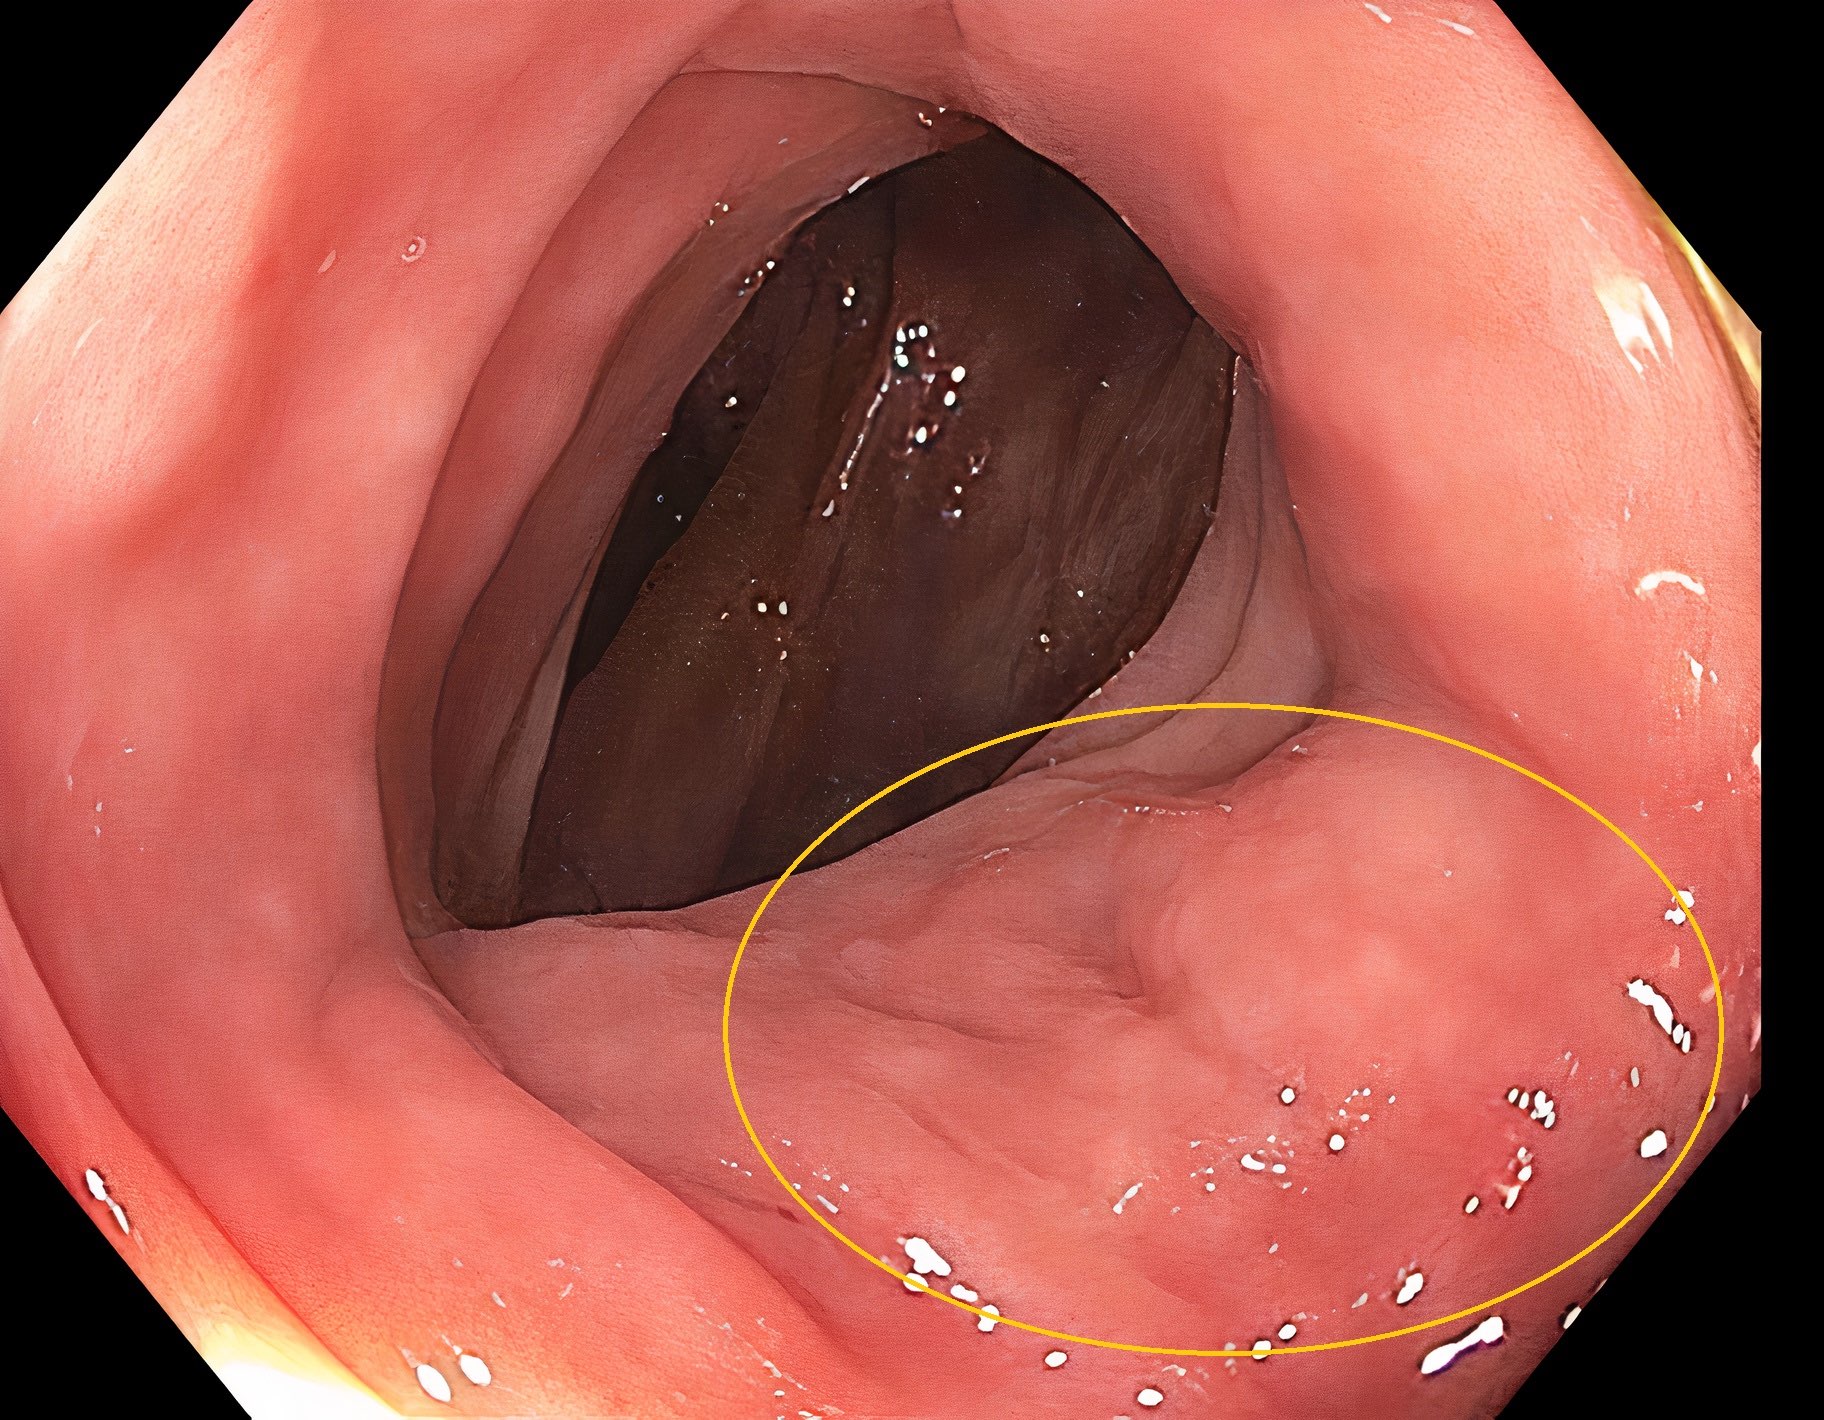

Clinical images

Gross description

- Specimen should be fixed and opened longitudinally for easy sampling of diverticula

- Usually, multiple flask shaped invaginations of colonic wall

- Wall thickening may be present (Surg Endosc 2011;25:2586)

- Narrowing of lumen, shortening of tenia and marked thickening of circular muscle layer may be present (J Clin Gastroenterol 2006;40:S108)

- If it extends deeply, perforation and serosal adhesions may be seen